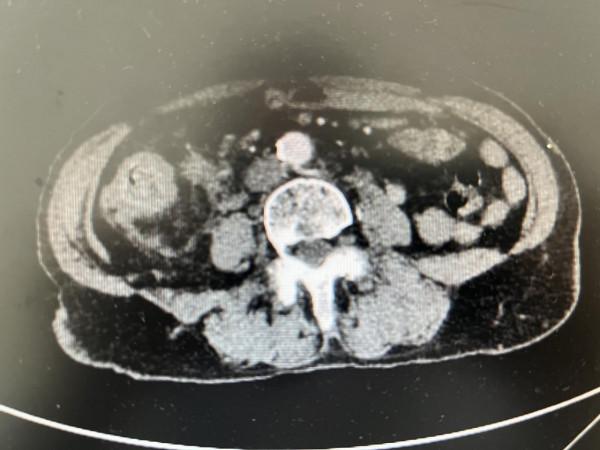

影像學檢查提示:1.升結腸及迴腸末端腸壁增厚,考慮惡性腫瘤;2.腹腔、腹膜後多發腫大淋巴結考慮轉移;3.腹腔內脂肪間隙模糊,腹膜增厚,考慮轉移的可能。

2021年9月20日,複查CT提示:1.結腸佔位,較前縮小;2.腹腔、腹膜後多發腫大淋巴結,後腹膜區腫大淋巴結較前縮小。

複查CT提示:1.結腸佔位,化療後改變;2.腹腔多發腫大淋巴結。